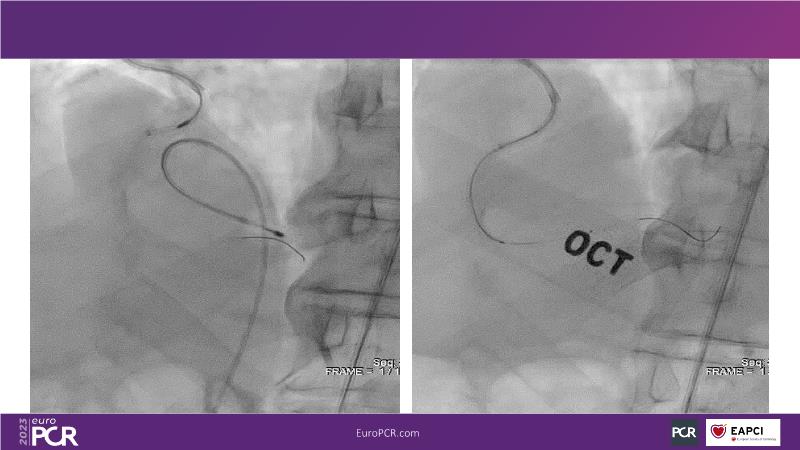

In this session, review the evolution in the use of IVL over the last few years, with a widening of the indications, observe that OCT can underestimate the number and depth of calcium fractured induced by IVL, or see that the technique is safe and effective in high-risk patients, including ACS patients, as demonstrated in real-world registries, among others!

- To understand how intravascular lithotripsy (IVL) in clinical practice has evolved over the last five years